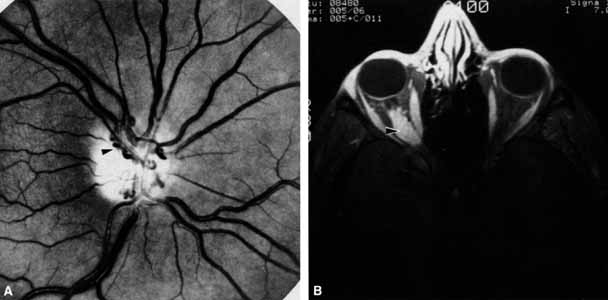

Blowout fractures of the orbit may result in ophthalmoplegia on either a restrictive or neurogenic basis.37 Restriction most often occurs due to entrapment of muscles, entrapment of orbital septae,38 or intrasheath hemorrhage with reduction of muscle compliance (Fig. 18). Less commonly, orbital emphysema secondary to blowout fractures, air hose injuries to the eye,39 or even subcutaneous emphysema entering the orbit may cause a restrictive ophthalmoplegia.40 It is also not uncommon for the inferior nerve branch of cranial nerve III to the inferior rectus and inferior oblique muscles to be damaged at the time of fracture. Entrapment is easily diagnosed with forced ductions, and the reduced velocity of infraducting saccades can help determine damage to the inferior nerve branch of cranial nerve III. Combined restrictive and neurogenic ophthalmoplegia may occur, clinically presenting as a blowout fracture with tissue herniation through a fractured orbital floor limiting upgaze. The muscle is extricated surgically from the fracture site and often, postoperatively, a large hypertropia develops. The inferior nerve branch of cranial nerve III is damaged, however, and the infraducting saccades may not have been checked prior to surgery. The ductions may well improve over time or resolve with strabismus surgery, but the patient may claim the damage to the third cranial nerve occurred intraoperatively. The moral is to always do a complete eye movements examination preoperatively.

Fig. 18 A. A 27-year-old woman sustained a blow to the left eye from a motor vehicle accident 3 days prior to this examination. Upgaze is limited on the left; the globe is ptotic and enophthalmic. B. Computed tomography scan demonstrates a large orbital floor fracture and a large inferior rectus muscle (arrow) that is not entrapped within the fracture. The extraocular movements improved to normal over the following 10 days but the enophthalmos increased.